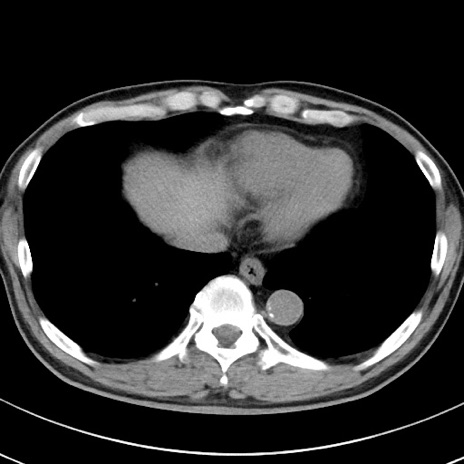

【腹部TIPS】症例29 参考症例 CT(横断像)

症例

70歳代男性